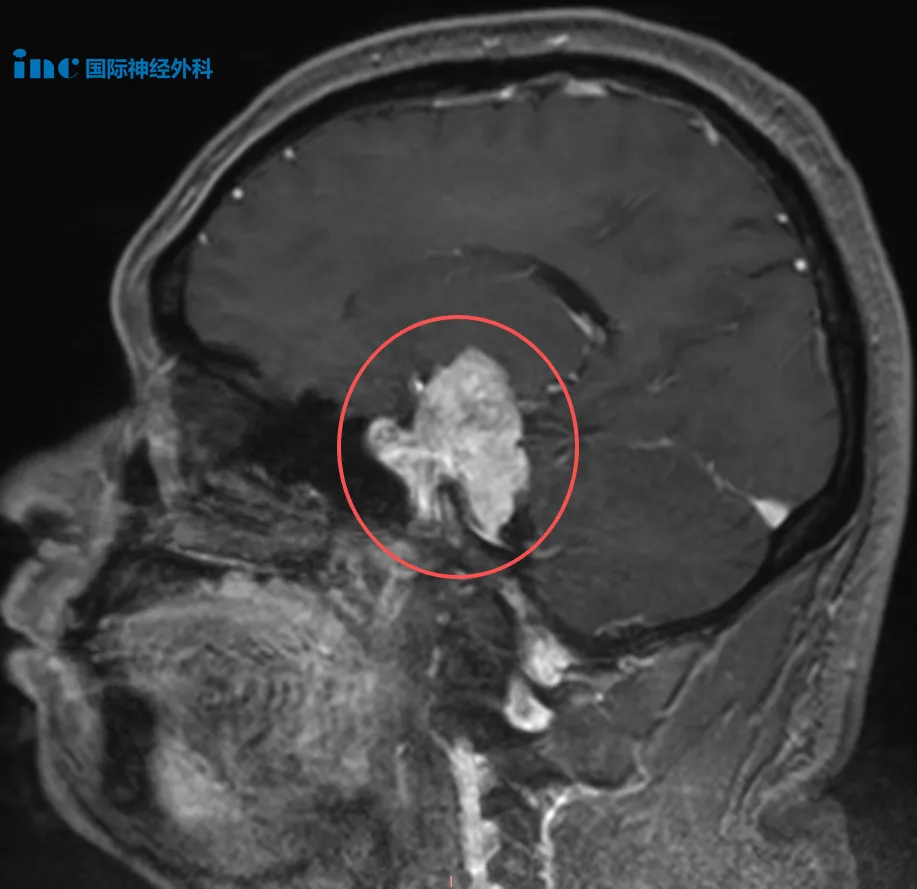

4、40岁男性左侧中、后颅窝占位性病变

吴先生,意外发现左侧中、后颅窝团块状异常强化影,大小约38mm×28mm,疑似脑膜瘤,且已压迫脑干。头昏不适,吴先生发现自己看东西越发模煳,记忆力也在下降。这样等下去会不会存在巨大的风险,令他陷入深深的恐惧。而咨询巴教授后,教授的评估与他的担心不谋而合,“继续拖延对患者没有好处,只会让肿瘤进一步发展,因为肿瘤在持续生长,越大手术就越复杂,手术应尽早进行。”

此外,巴教授表示吴先生的脑膜瘤非常罕见,它有不寻常的生长延伸:一方面向上延伸到左侧大脑内部,推压基底节、颞叶和下丘脑,同时影响视系统,包括视神经和视交叉;另一方面,它还有相当大的一部分在幕下。肿瘤跨越了两个不同的颅内间隙:颞叶区域和后颅窝。这种向上又向下的双向延伸需要采用特别的手术技术。